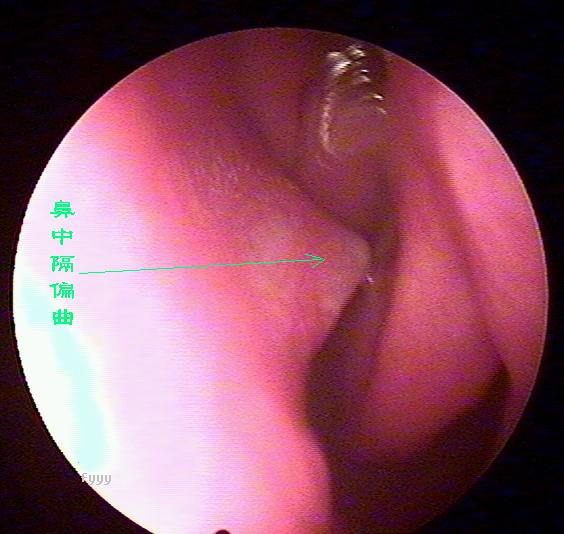

鼻内窥镜下的鼻中隔偏曲

老流鼻血可能是鼻中隔偏曲惹的祸,鼻中隔偏曲部位经常会出现血管畸形,而且这里的粘膜也相对较薄,受气流、尘埃等刺激后容易破损、出血,主要症状为:交替性或持续性鼻塞,头痛,鼻出血及流脓涕等。且难以痊愈,经常发作。西安新城中大耳鼻喉医院耳鼻喉科推出的微创手术,快速无痛治疗鼻中隔偏曲。